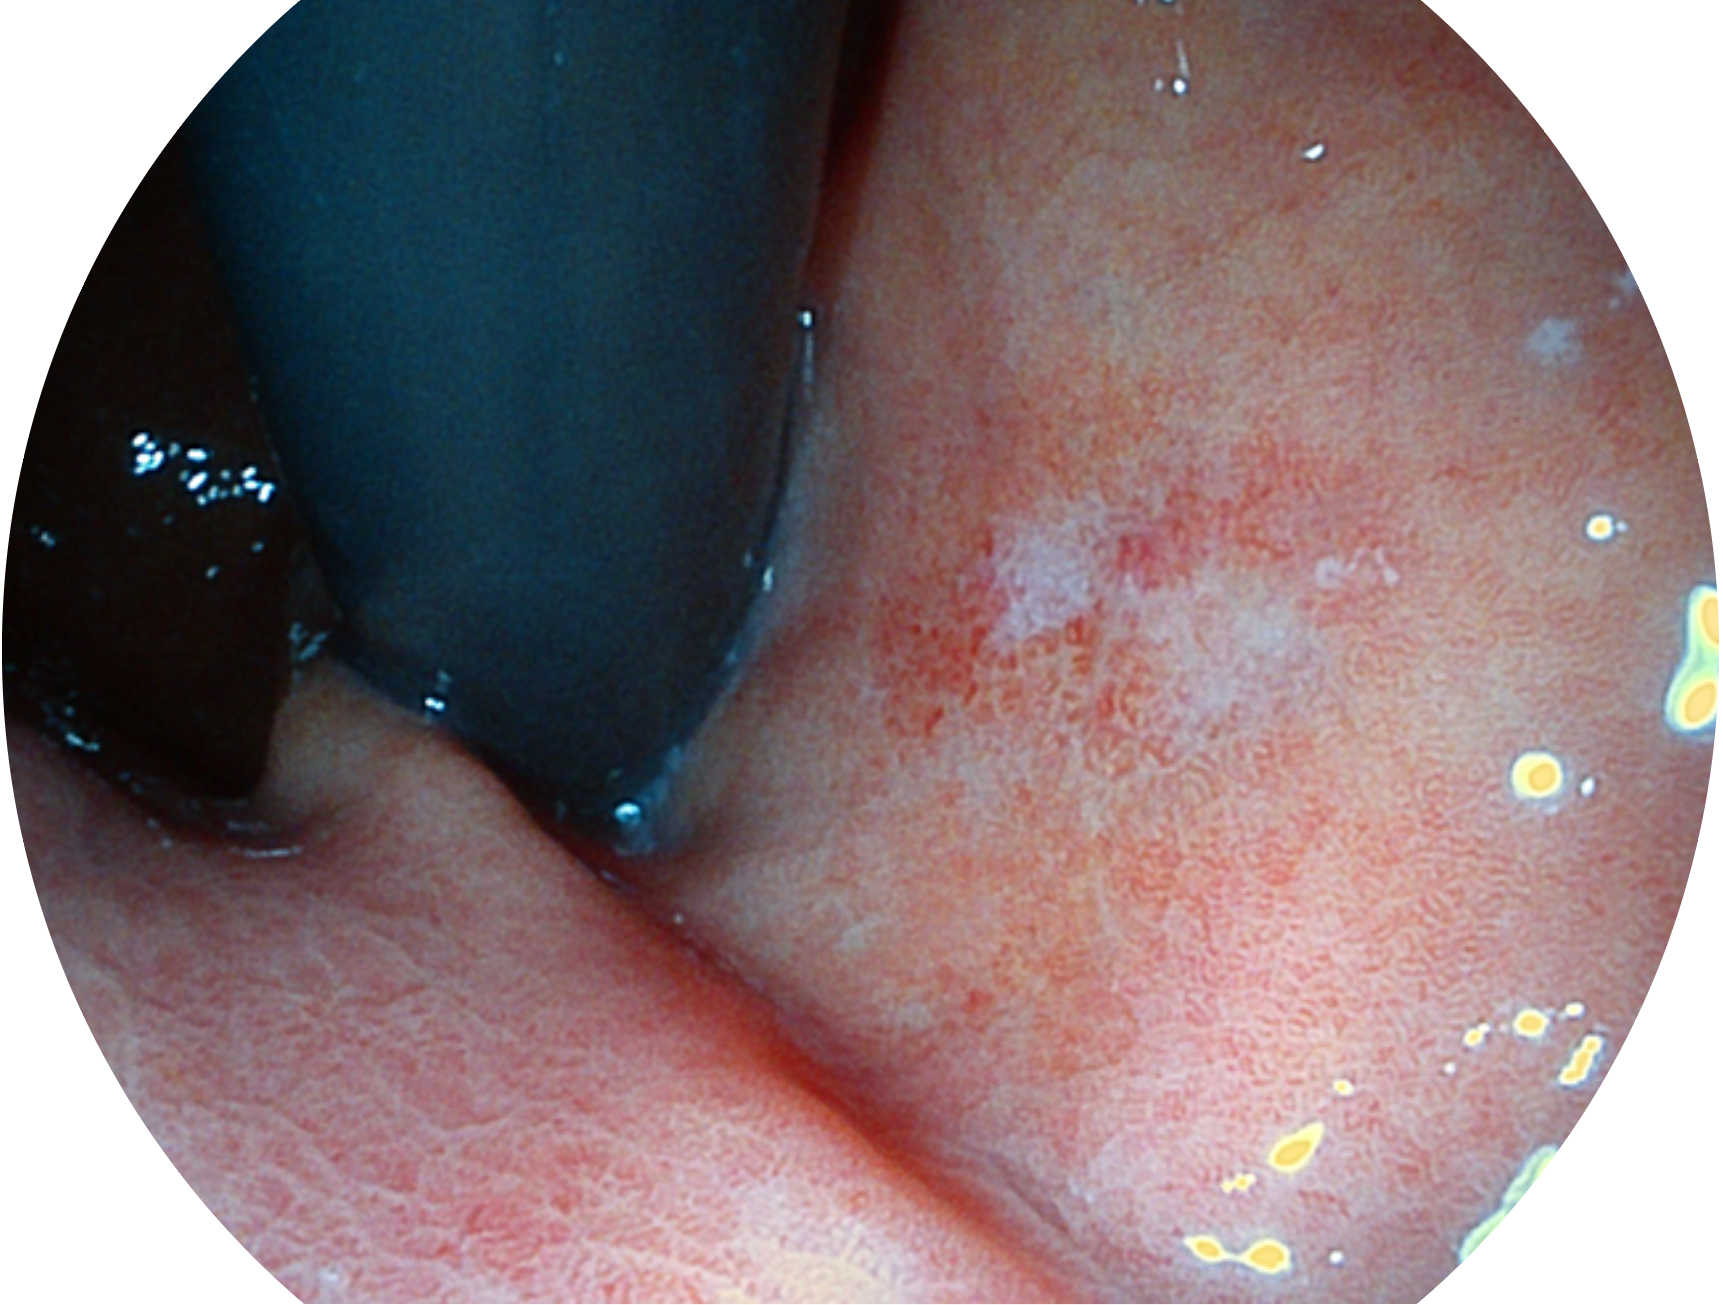

球速体育入口新开发的内镜染色技术,主要是基于多波长LED 光源的开发,VLS-55Q 四波长LED 光源是由四个不同颜色的LED光按照相应照明模式所规定的特定发光比例进行合束后形成,合束后形成的照明光的光谱由红光、绿光、蓝光及蓝紫光这四个不同的波段范围构成。具有更高光谱自由度,通过光谱比例的控制,实现了聚谱成像技术,英文全称为“Spectral Focused Imaging, SFI”,缩写为“SFI”和光电复合染色成像技术,英文全称为“Versatile Intelligent Staining Technology, VIST”,缩写为“VIST”。